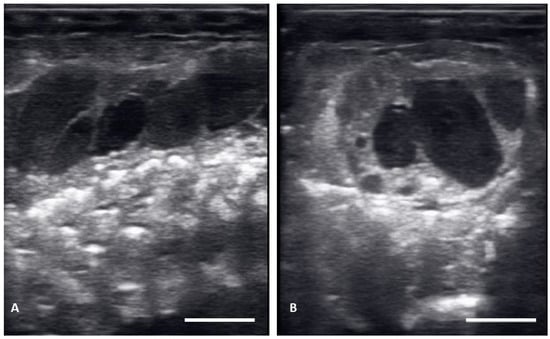

| Post ovulatory follicles (POV) | Ovulated follicles, passed into the oviduct showing an hypoechoic surrounding, but no visible calcified layer. |

| Shelled eggs (Shell) | Ovulated follicles, passed into the oviduct and surrounded by a calcified layer. |